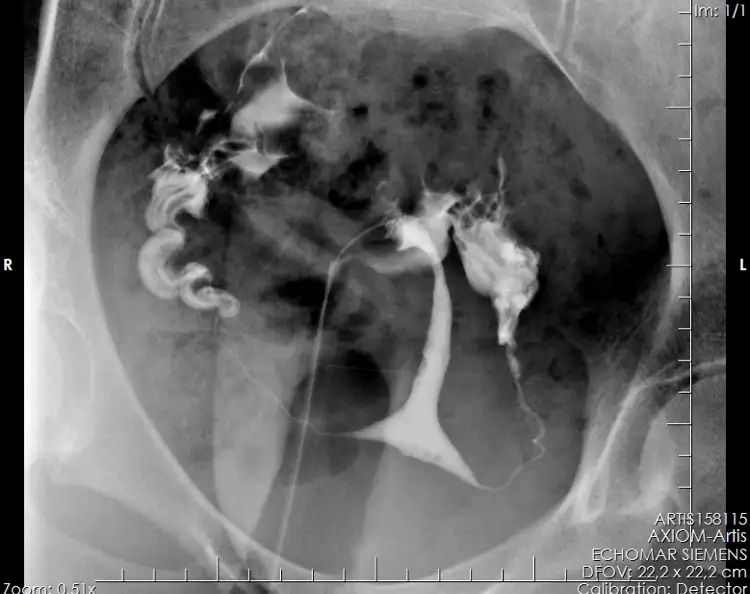

3.5 senelik evliyim ve 2.5 senedir sebepsiz infertilite ile cebelleşiyorum. Bu süreçte klasik Klomen, Ovitrelle gibi tedaviler uygulandı. Eşimde ve bende bir sorun yok şükür. Sadece benim rahim filmimin sonucuna göre hafif T şekli olabilir dendi. Bazı doktorlar onu bile demedi ki rahim filmini çeken doktorun raporunda da böyle bir sonuç yazmıyor. (Rahim filmim aşağıda ekli.)